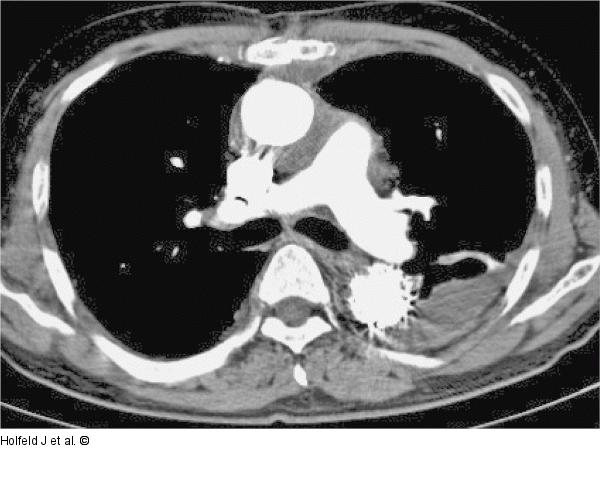

Abbildung 4: CT Postoperatives CT. Der Patient erhielt einen klappenerhaltenden Ascendens- und Wurzelersatz (David-OP) sowie einen kompletten Bogenersatz. Darüber hinaus wurde intraoperativ die Aorta descendens mittels zweier Stentgrafts versorgt. |

Postoperatives CT. Der Patient erhielt einen klappenerhaltenden Ascendens- und Wurzelersatz (David-OP) sowie einen kompletten Bogenersatz. Darüber hinaus wurde intraoperativ die Aorta descendens mittels zweier Stentgrafts versorgt. |